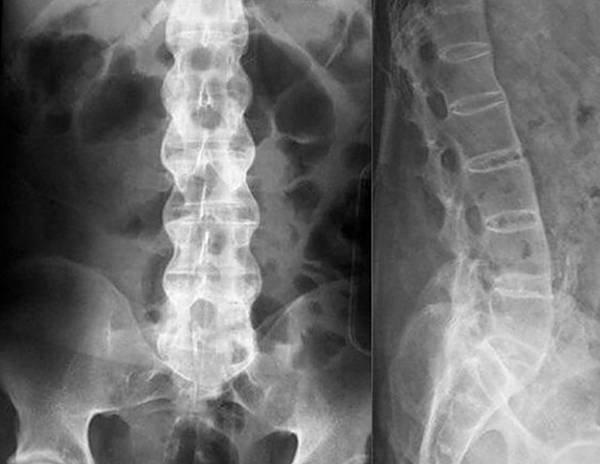

При болях в ноге при остеохондрозе не наблюдаются отеки, иногда может быть слабость в нижних конечностях. Если мерзнет нога в области стоп или голени, следует сделать рентгеновский снимок. Скорее всего, заболевание затронуло корешки L III.

Если симптомы явно указывают на грыжу, остеохондроз или радикулит, для диагностики обычно применяют рентгенологическое исследование. Рентгенография относится к самым простым и доступным способам, к тому же, для снимка требуется совсем немного времени, в отличие от КТ, где пациент должен сохранять неподвижность достаточно долго. Для оценки состояния сосудов и мягких тканей назначают УЗИ, а при подозрении на инфекционную природу недуга обязательно проводятся лабораторные исследования крови и мочи. По полученным результатам врач подбирает больному оптимальный способ лечения.

При заболеваниях позвоночника чаще всего для диагностики применяют рентгенографию